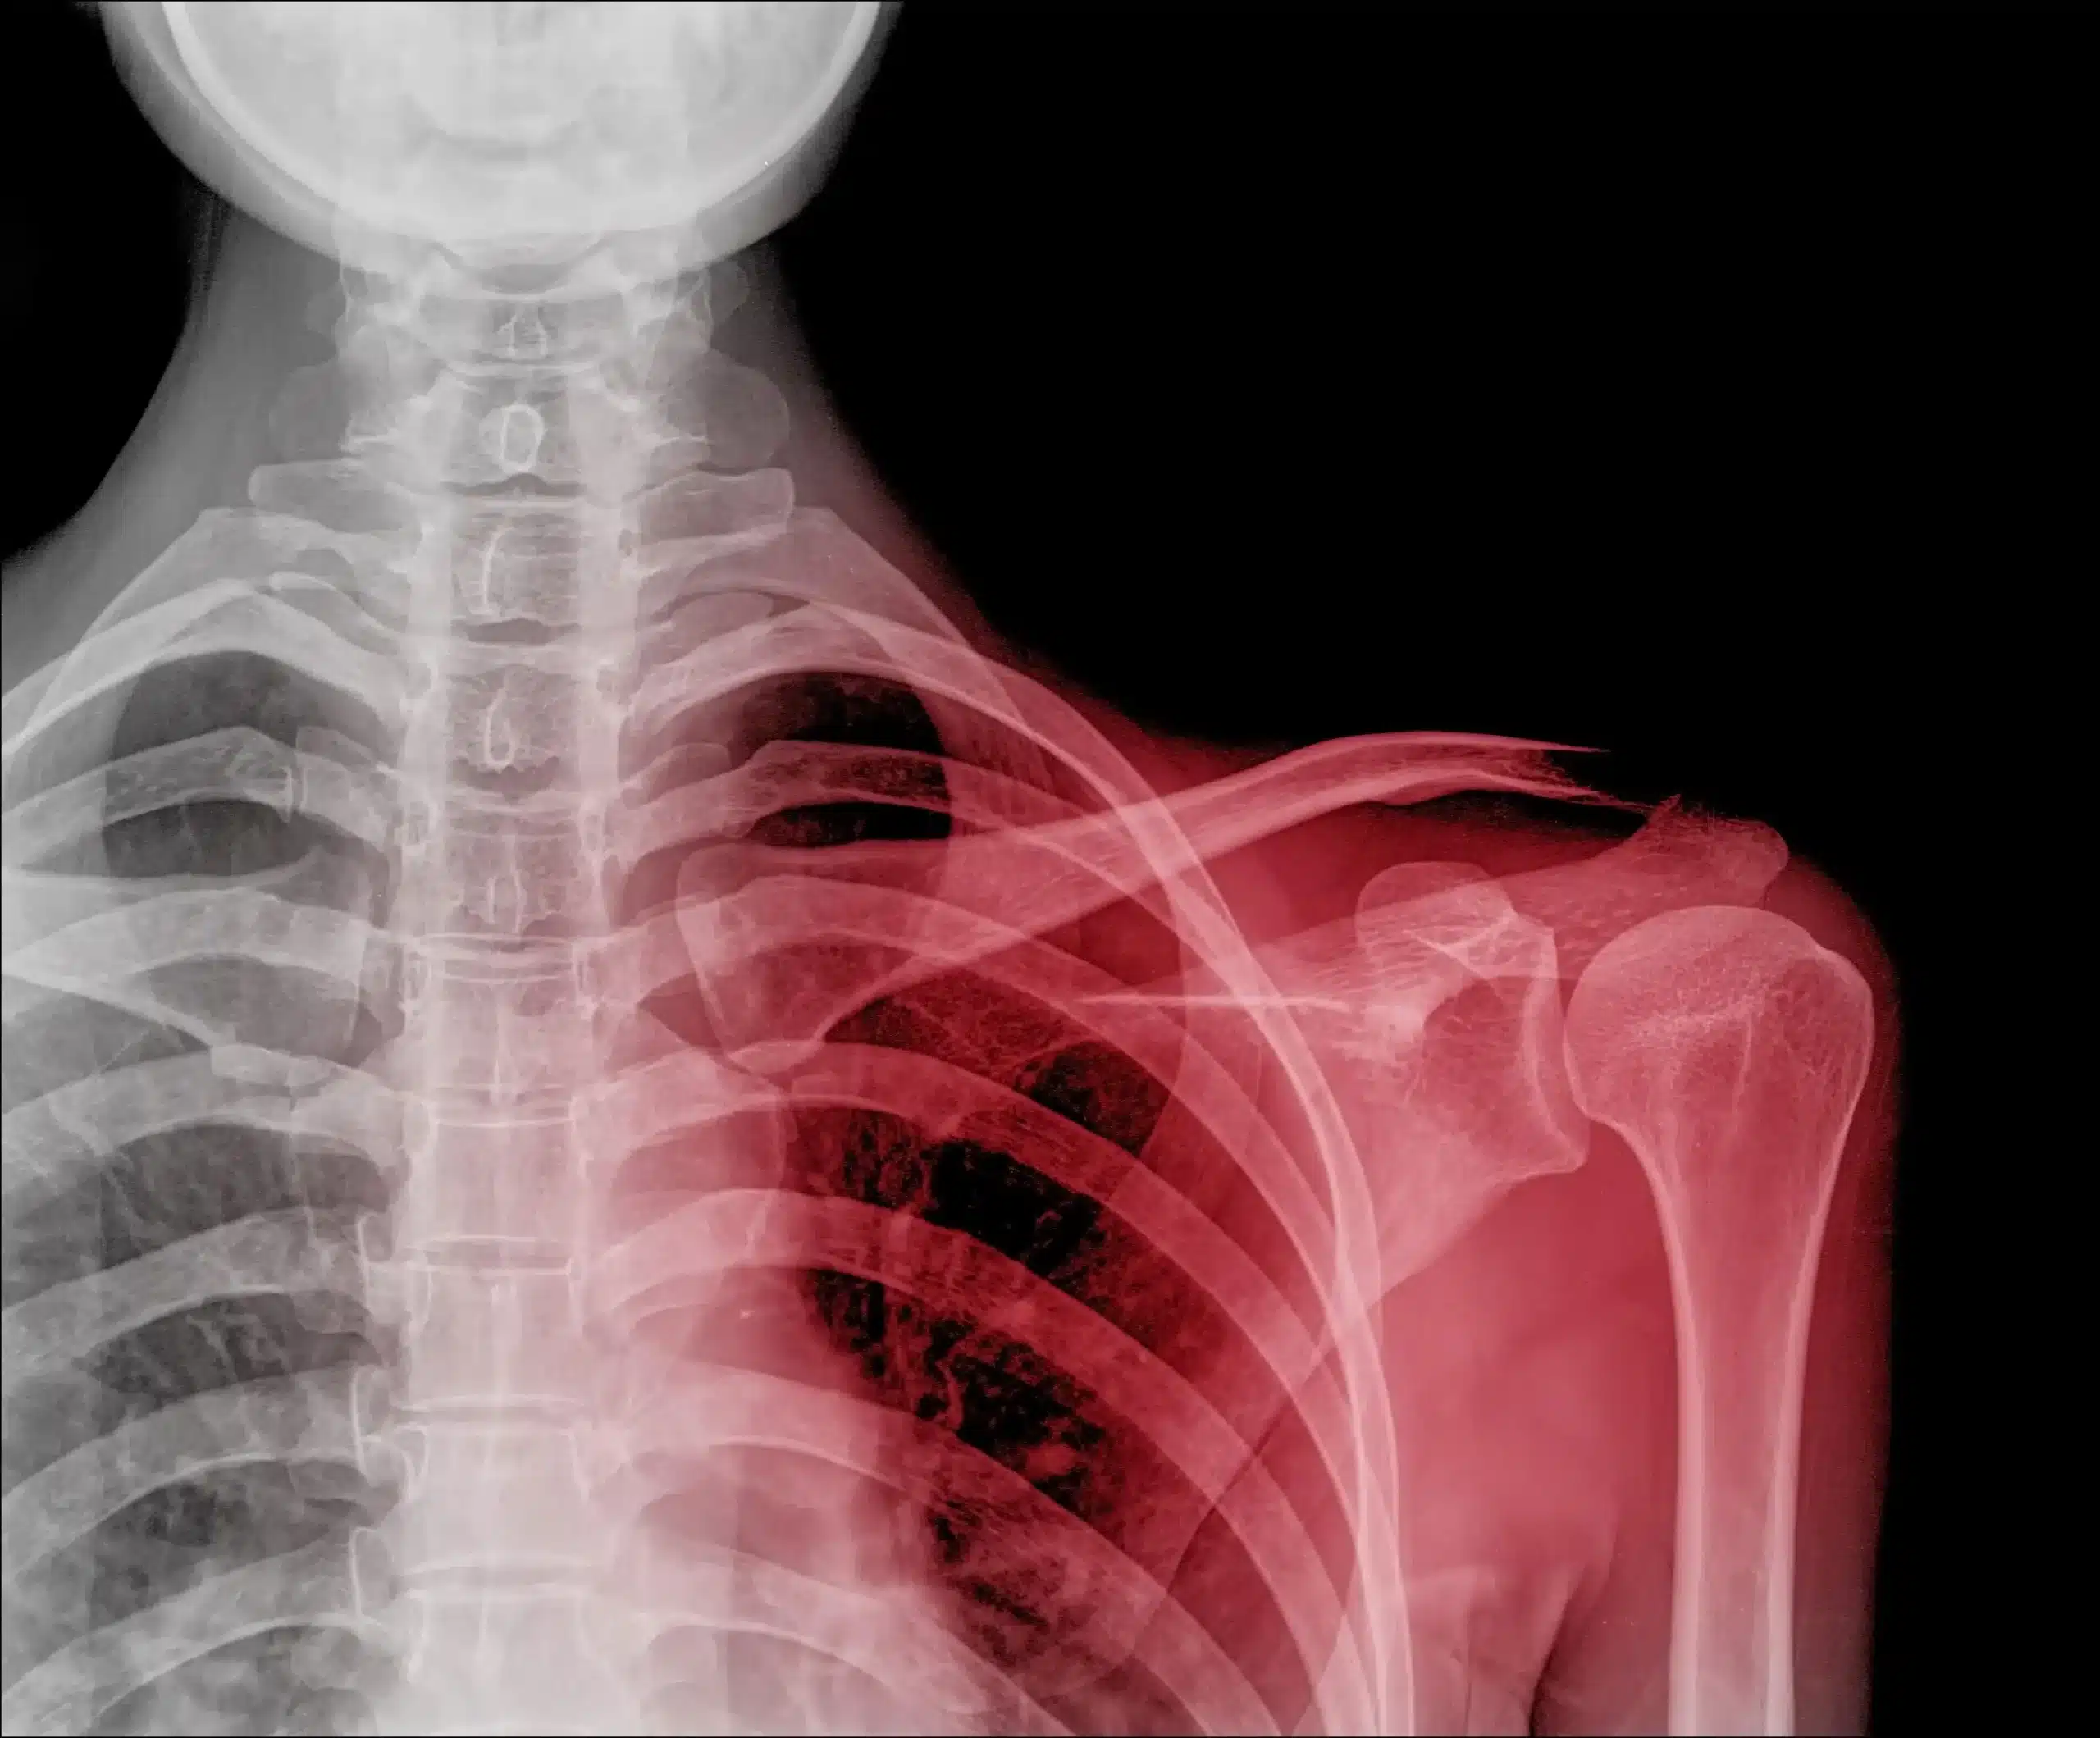

دررفتگی مفصل شانه: آسیب شانه، به ویژه دررفتگی مفصل شانه، یک مشکل نسبتاً شایع است که می تواند باعث درد شدید، ضعف و محدودیت حرکت شود. دررفتگی مفصل شانه زمانی اتفاق می افتد که استخوان بالایی بازو (استخوان هومروس) از حفره مفصل شانه خارج شود. این آسیب اغلب در اثر ضربه مستقیم به شانه، زمین خوردن روی دست یا بازو یا حرکات ناگهانی و شدید شانه ایجاد می شود.

تشخیص دررفتگی مفصل شانه معمولا توسط پزشک متخصص ارتوپدی انجام می شود. پزشک ابتدا شرح حال بیمار را به طور کامل دریافت می کند و سپس به معاینه فیزیکی مفصل شانه می پردازد. در معاینه فیزیکی، پزشک به دنبال نقاط حساس به درد، تورم، تغییر شکل مفصل و محدودیت دامنه حرکتی مفصل شانه می گردد. در برخی موارد، برای تایید تشخیص و افتراق دررفتگی مفصل شانه از سایر مشکلات شانه، ممکن است پزشک درخواست انجام تصویربرداری اشعه ایکس یا سی تی اسکن دهد.